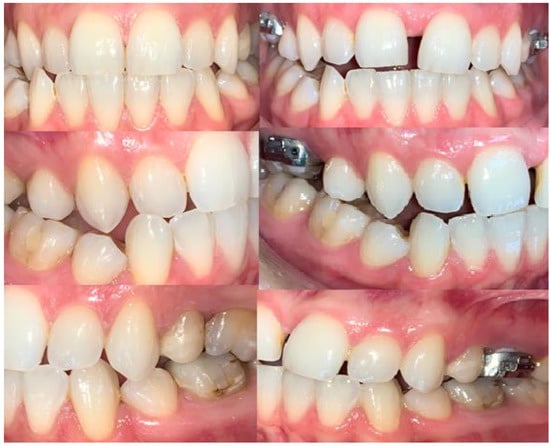

2.2. Clinical Outcomes